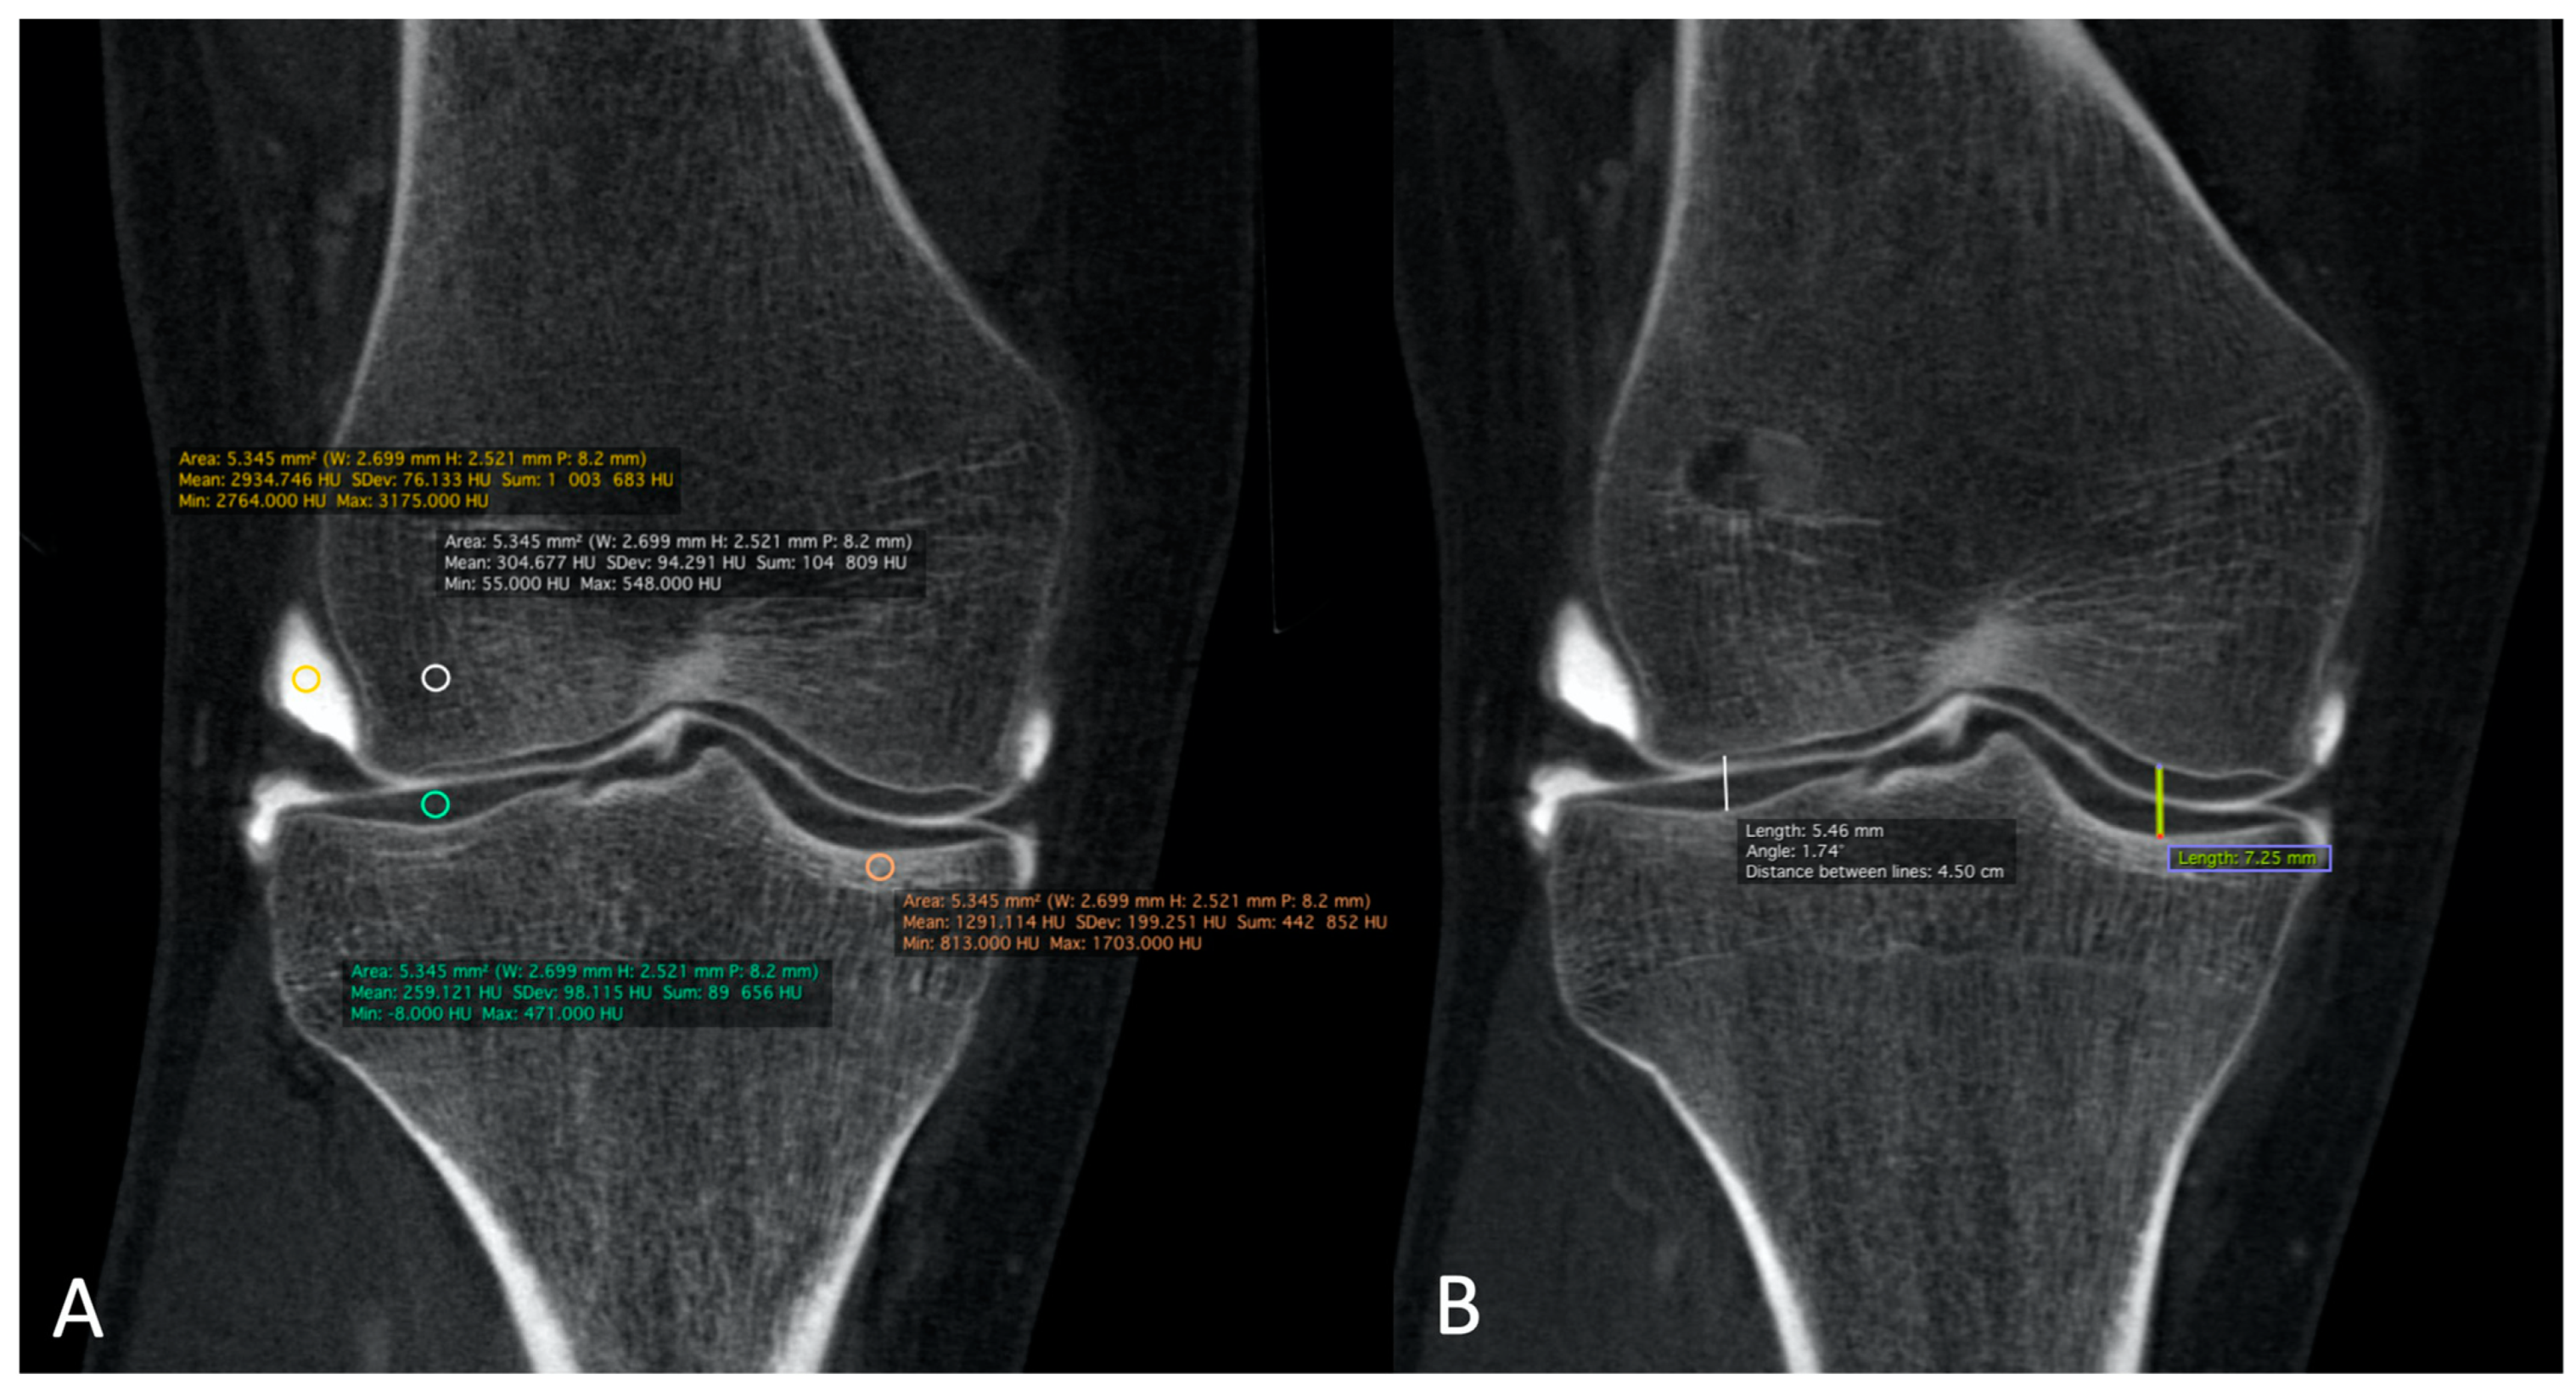

1. Introduction

2.1. Patient Population

2.3. Qualitative Image Analysis for CBCT-A

2.4. Quantitative Image Analysis of CBCT-A